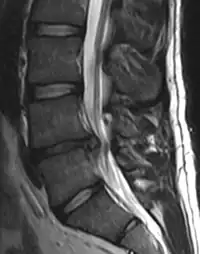

- Magnetic resonance imaging is the gold standard study for confirming a suspected LDH. With a diagnostic accuracy of 97%, it is the most sensitive study to visualize a herniated disc due to its significant ability in soft tissue visualization. MRI also has higher inter-observer reliability than other imaging modalities. It suggests disc herniation when it shows an increased T2-weighted signal at the posterior 10% of the disc. Degenerative disc diseases have shown a correlation with Modic type 1 changes. When evaluating for postoperative lumbar radiculopathies, the recommendation is that the MRI is performed with contrast unless otherwise contraindicated. MRI is more effective than CT in distinguishing inflammatory, malignant, or inflammatory etiologies of LDH. It is indicated relatively early in the course of evaluation (<8 weeks) when the patient presents with relative indications like significant pain, neurological motor deficits, and cauda equina syndrome. Diffusion tensor imaging is a type of MRI sequence used for detecting microstructural changes in the nerve root. It may be beneficial in understanding the changes that occur after herniated lumbar disc compresses a nerve root, and might help in differentiating the patients that need surgical intervention. In patients with a high suspicion of radiculopathy due to lumbar disc herniation, yet the MRI is equivocal or negative, nerve conduction studies are indicated.[43] T2-weighted images allow for clear visualization of protruded disc material in the spinal canal.

MRI scan of large herniation (on the right) of the disc between L4 and L5 vertebrae

A rather severe herniation of the L4–L5 disc

Example of a herniated disc at L5–S1 in the lumbar spine